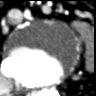

Native data are sequences of CT images in basal mode and with contrast medium (CM), acquired, in Hounsfield scale, in bit DICOM format.

The images used have been provided by the Division of Diagnostic Imaging of the Department of Medicine and Surgery of the University of Perugia, belonging to six patients with AAA and to whom the contrast medium could be administered; furthermore, prior to undergoing the CT scan, they have signed an informed consent. The thikness of the slices is about mm, and the parameters of the windowing are and for the basal sequence, and for the contrast medium one.

As we can see from Figure 3, the sequences have been anonymized, by converting the images from DICOM to the lossless portable network graphics (.png) format, pixel resolution, bit grey-levels.